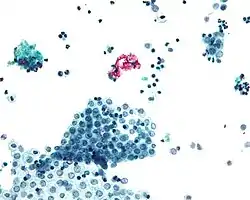

- Mesothelioma: (cancer of the mesothelium) is a disease in which cells of the mesothelium become abnormal and divide without control or order. They can invade and damage nearby tissues and organs. Cancer cells can also metastasize (spread) from their original site to other parts of the body. Most cases of mesothelioma begin in the pleura or peritoneum. More than 90% of mesothelioma cases are linked to asbestos exposure.